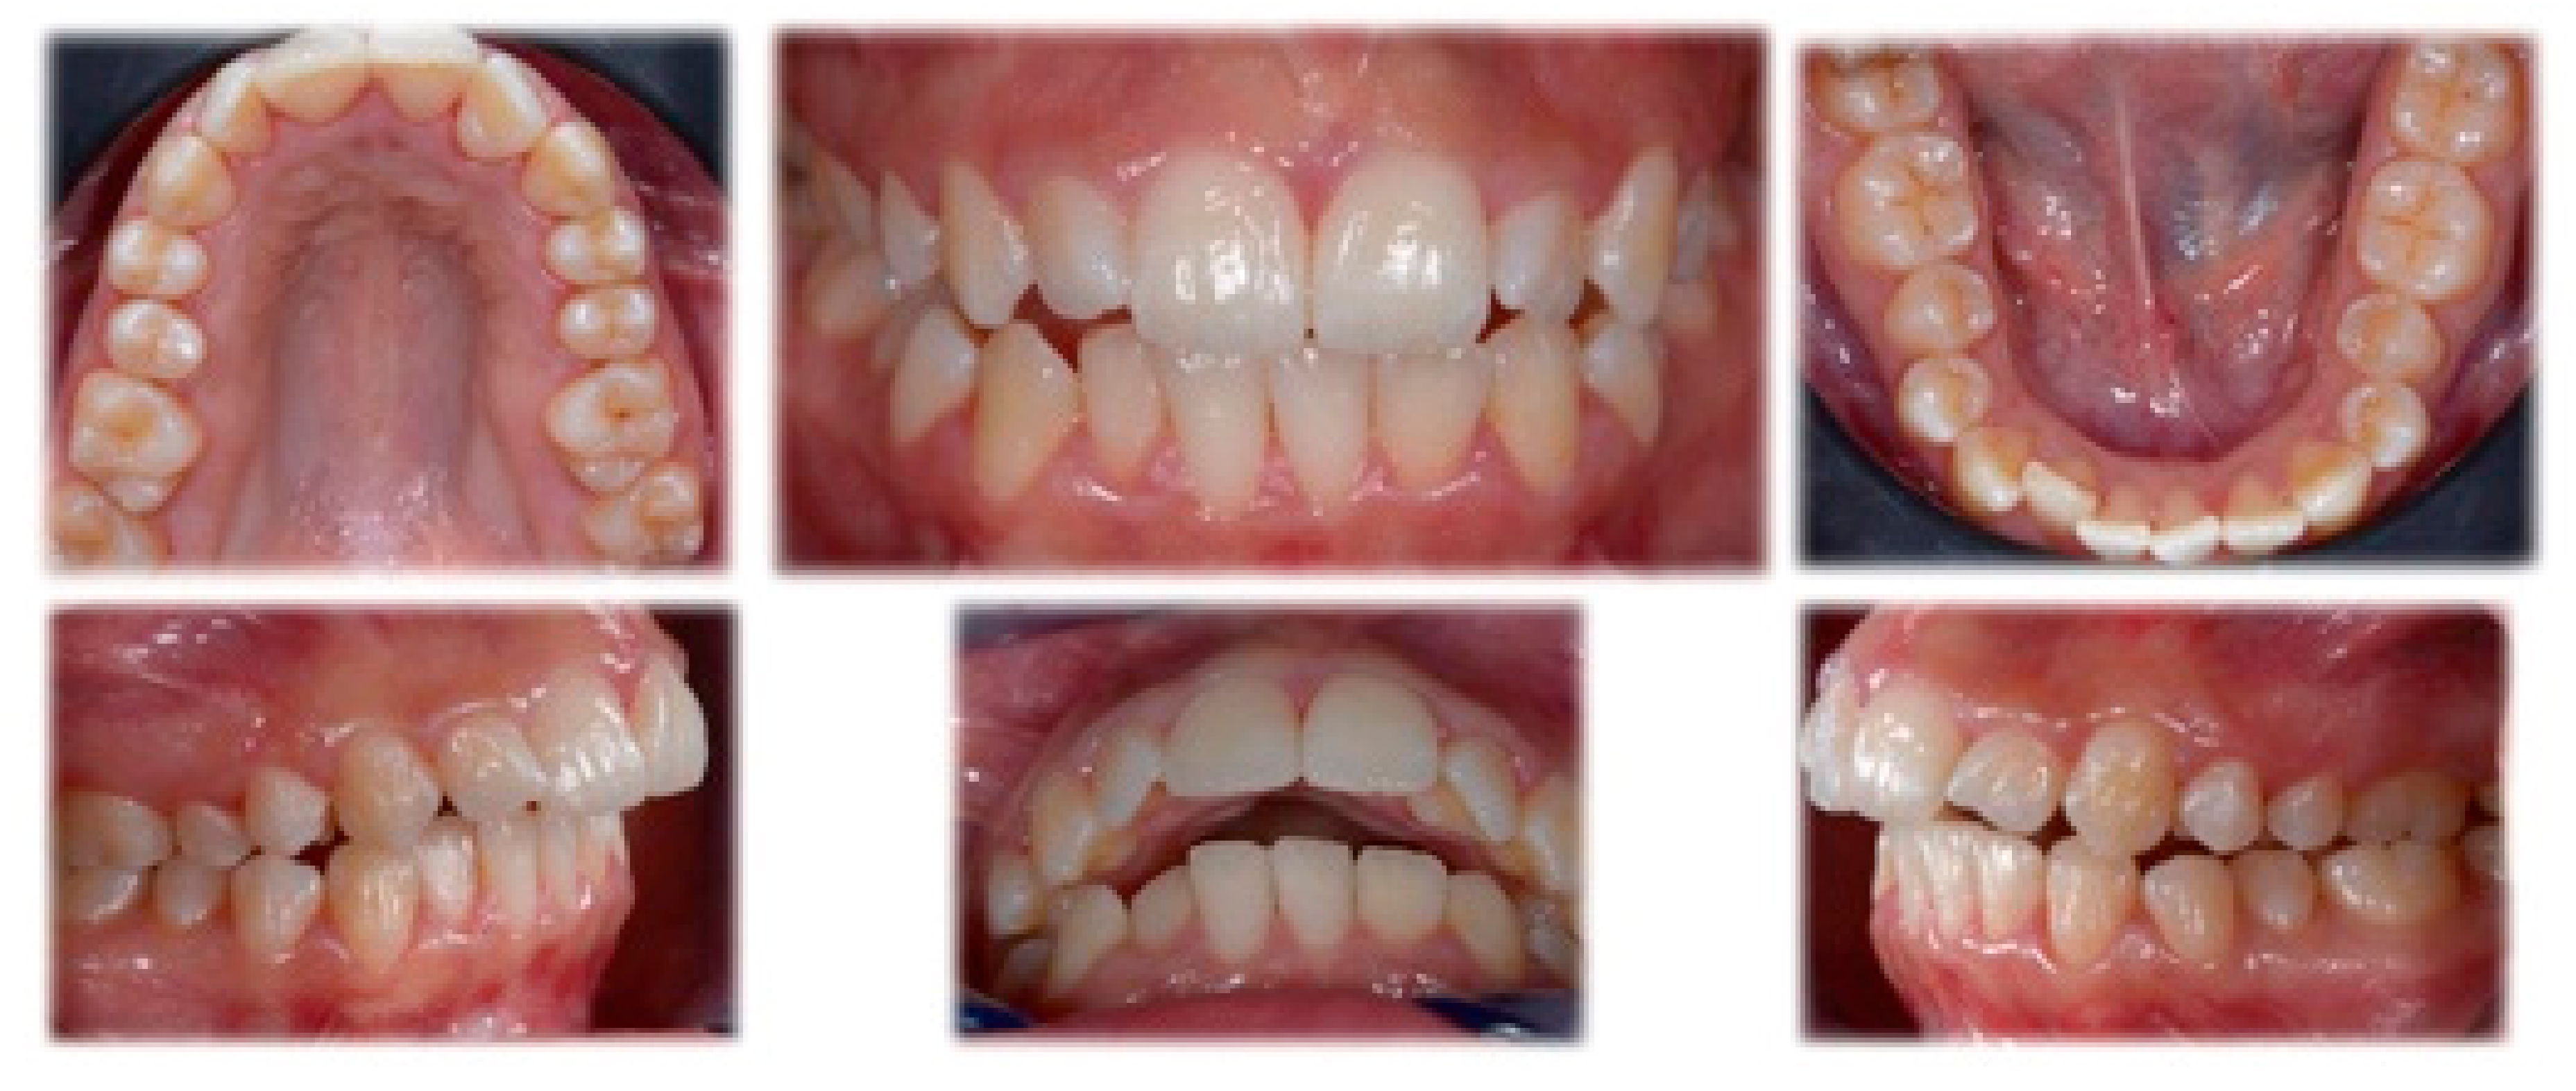

Intraoral evaluation and analysis showed an asymmetric occlusion with a full-cusp Class II molar and canine relationship on the right side and a Class I molar and end-on canine relationship on the left side. The overjet was 9 mm with a slight open bite on the lateral incisors and 1 mm overbite on the central incisors (Figure 2).

Figure 2.

Pre-treatment intraoral records and X-rays showing full-cusp Class II molar and canine relationship on the right side, Class I molar and end-on canine relationship on the left side, with increased overjet and slight open-bite on the lateral incisors.

Evaluation of X-rays (Dentsply Sirona, York, PA, USA) revealed the presence of an impacted upper third molar; the lower third molars were already erupted. Cephalometric analysis confirmed a normodivergent skeletal pattern with wide symphysis and optimal position and inclination of lower incisors. The upper incisors were proclined and protruded with respect to the anterior nasal spine.